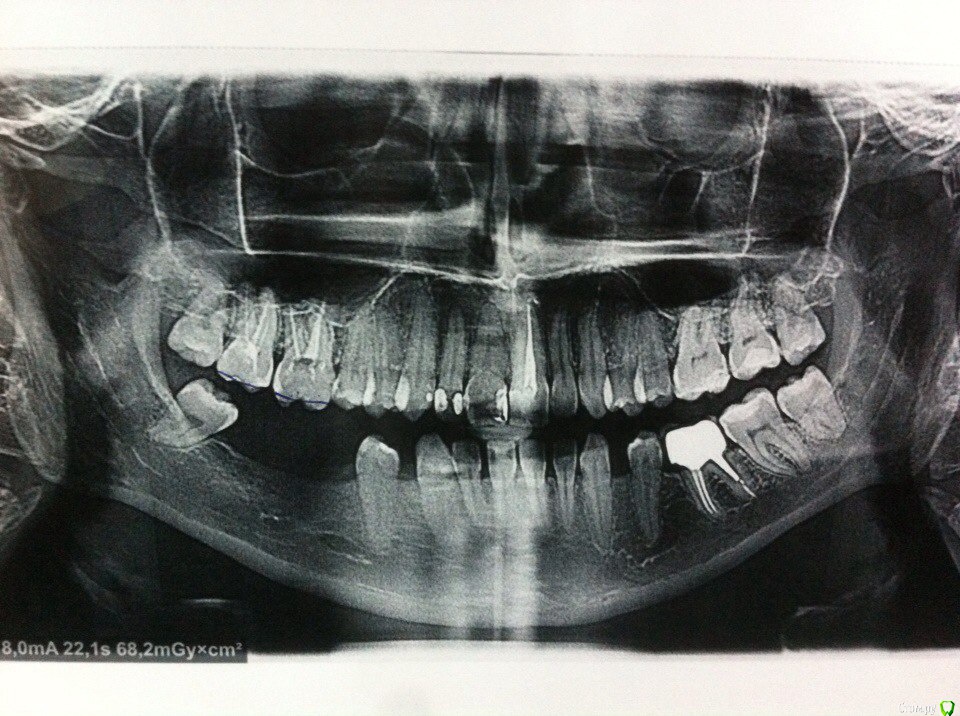

nasya Опубликовано 15 июля, 2017 Поделиться Опубликовано 15 июля, 2017 (изменено) Здравствуйте,уважаемые специалисты, и так же пациенты с подобной проблемой.Буду очень благодарна, если Вы поможете мне с правильным решением, и так же с историями других пациентов, переживших что-то подобное. Заранее всем спасибо! Мне удалили 6-ку и 7-ку нижней челюсти, на одной стороне, 3 года назад, за это времяпроизошла сильная атрофия, кость истончалась настолько, что мнекажется она в толщину 3 мм. Соответственно ставить импланты абсолютно неначто. Год ношу сьемный протез, и от этого она кажется еще больше и опустилась, соответственно вниз и поехал вниз верхнийряд зубов, не сильно но изминения есть , в сторону к щеке и вниз. Жевать совсем не комфортно.Врачи говорят ситуация очень сложная,еще в том, что близко расположен ч.л нерв, который можно задеть. Еслиговорить об остеопластике, то блок можно взять только с подвздошнойкости, потому что больше не откуда, в чл не хватает,не в подбородке,не еще где-то там. Предложили базальную имплантацию, но учитывая насколько тонкая кость, у меня не укладывается в голове, как импланты будут держаться и на чем, потом переломают челюсть, мне кажется, и видела фото такого плана баз.имплантации, где штифты со временем оголялись, и это ужасно выглядело все, так вот, сопоставив все эти факторы, я поняла что этот вариант только комерция частных клиник, и не поверила этому. Ортодонт сказал до операции(если делать) нужно год носить брекеты перед этим, что бы поставить правильной формы коронки и поднять верхний ряд. Здесь вопрос уже о страхе и риске, носить брекеты, а если кость не приживется, то все насмарку..Я все равно верю в чудо и в свои мысли позитива, что будет все хорошо конечно, хотелось бы просто получить статистику таких операций и вдохновения от врача и пациентов, у которых подобное закончилось хэпи-эндом!) Изменено 15 июля, 2017 пользователем nasya Ссылка на комментарий

rivezico Опубликовано 15 июля, 2017 Поделиться Опубликовано 15 июля, 2017 Дорый день, нужен КТ снимок. Ссылка на комментарий